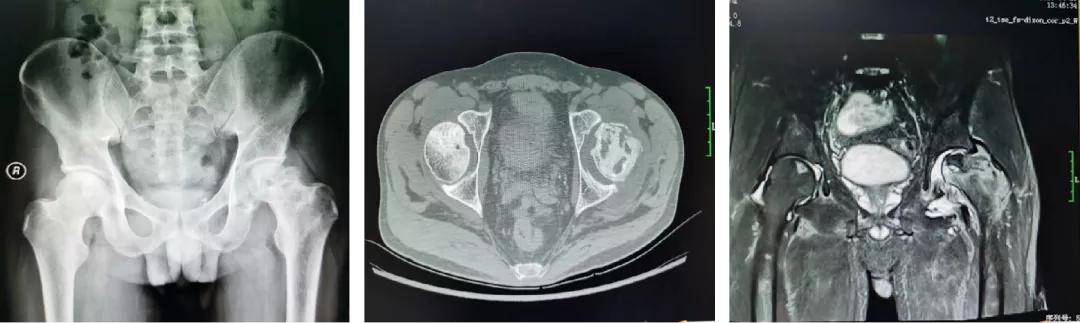

案例二

35岁的覃先生,也是双侧股骨头坏死,经同事介绍到关节与运动医学科住院,选择左侧人工全髋关节置换术、右侧机器人辅助下保髋治疗,术后效果良好,患者及其家属非常满意。

术前辅助检查

右侧保髋、左侧THA